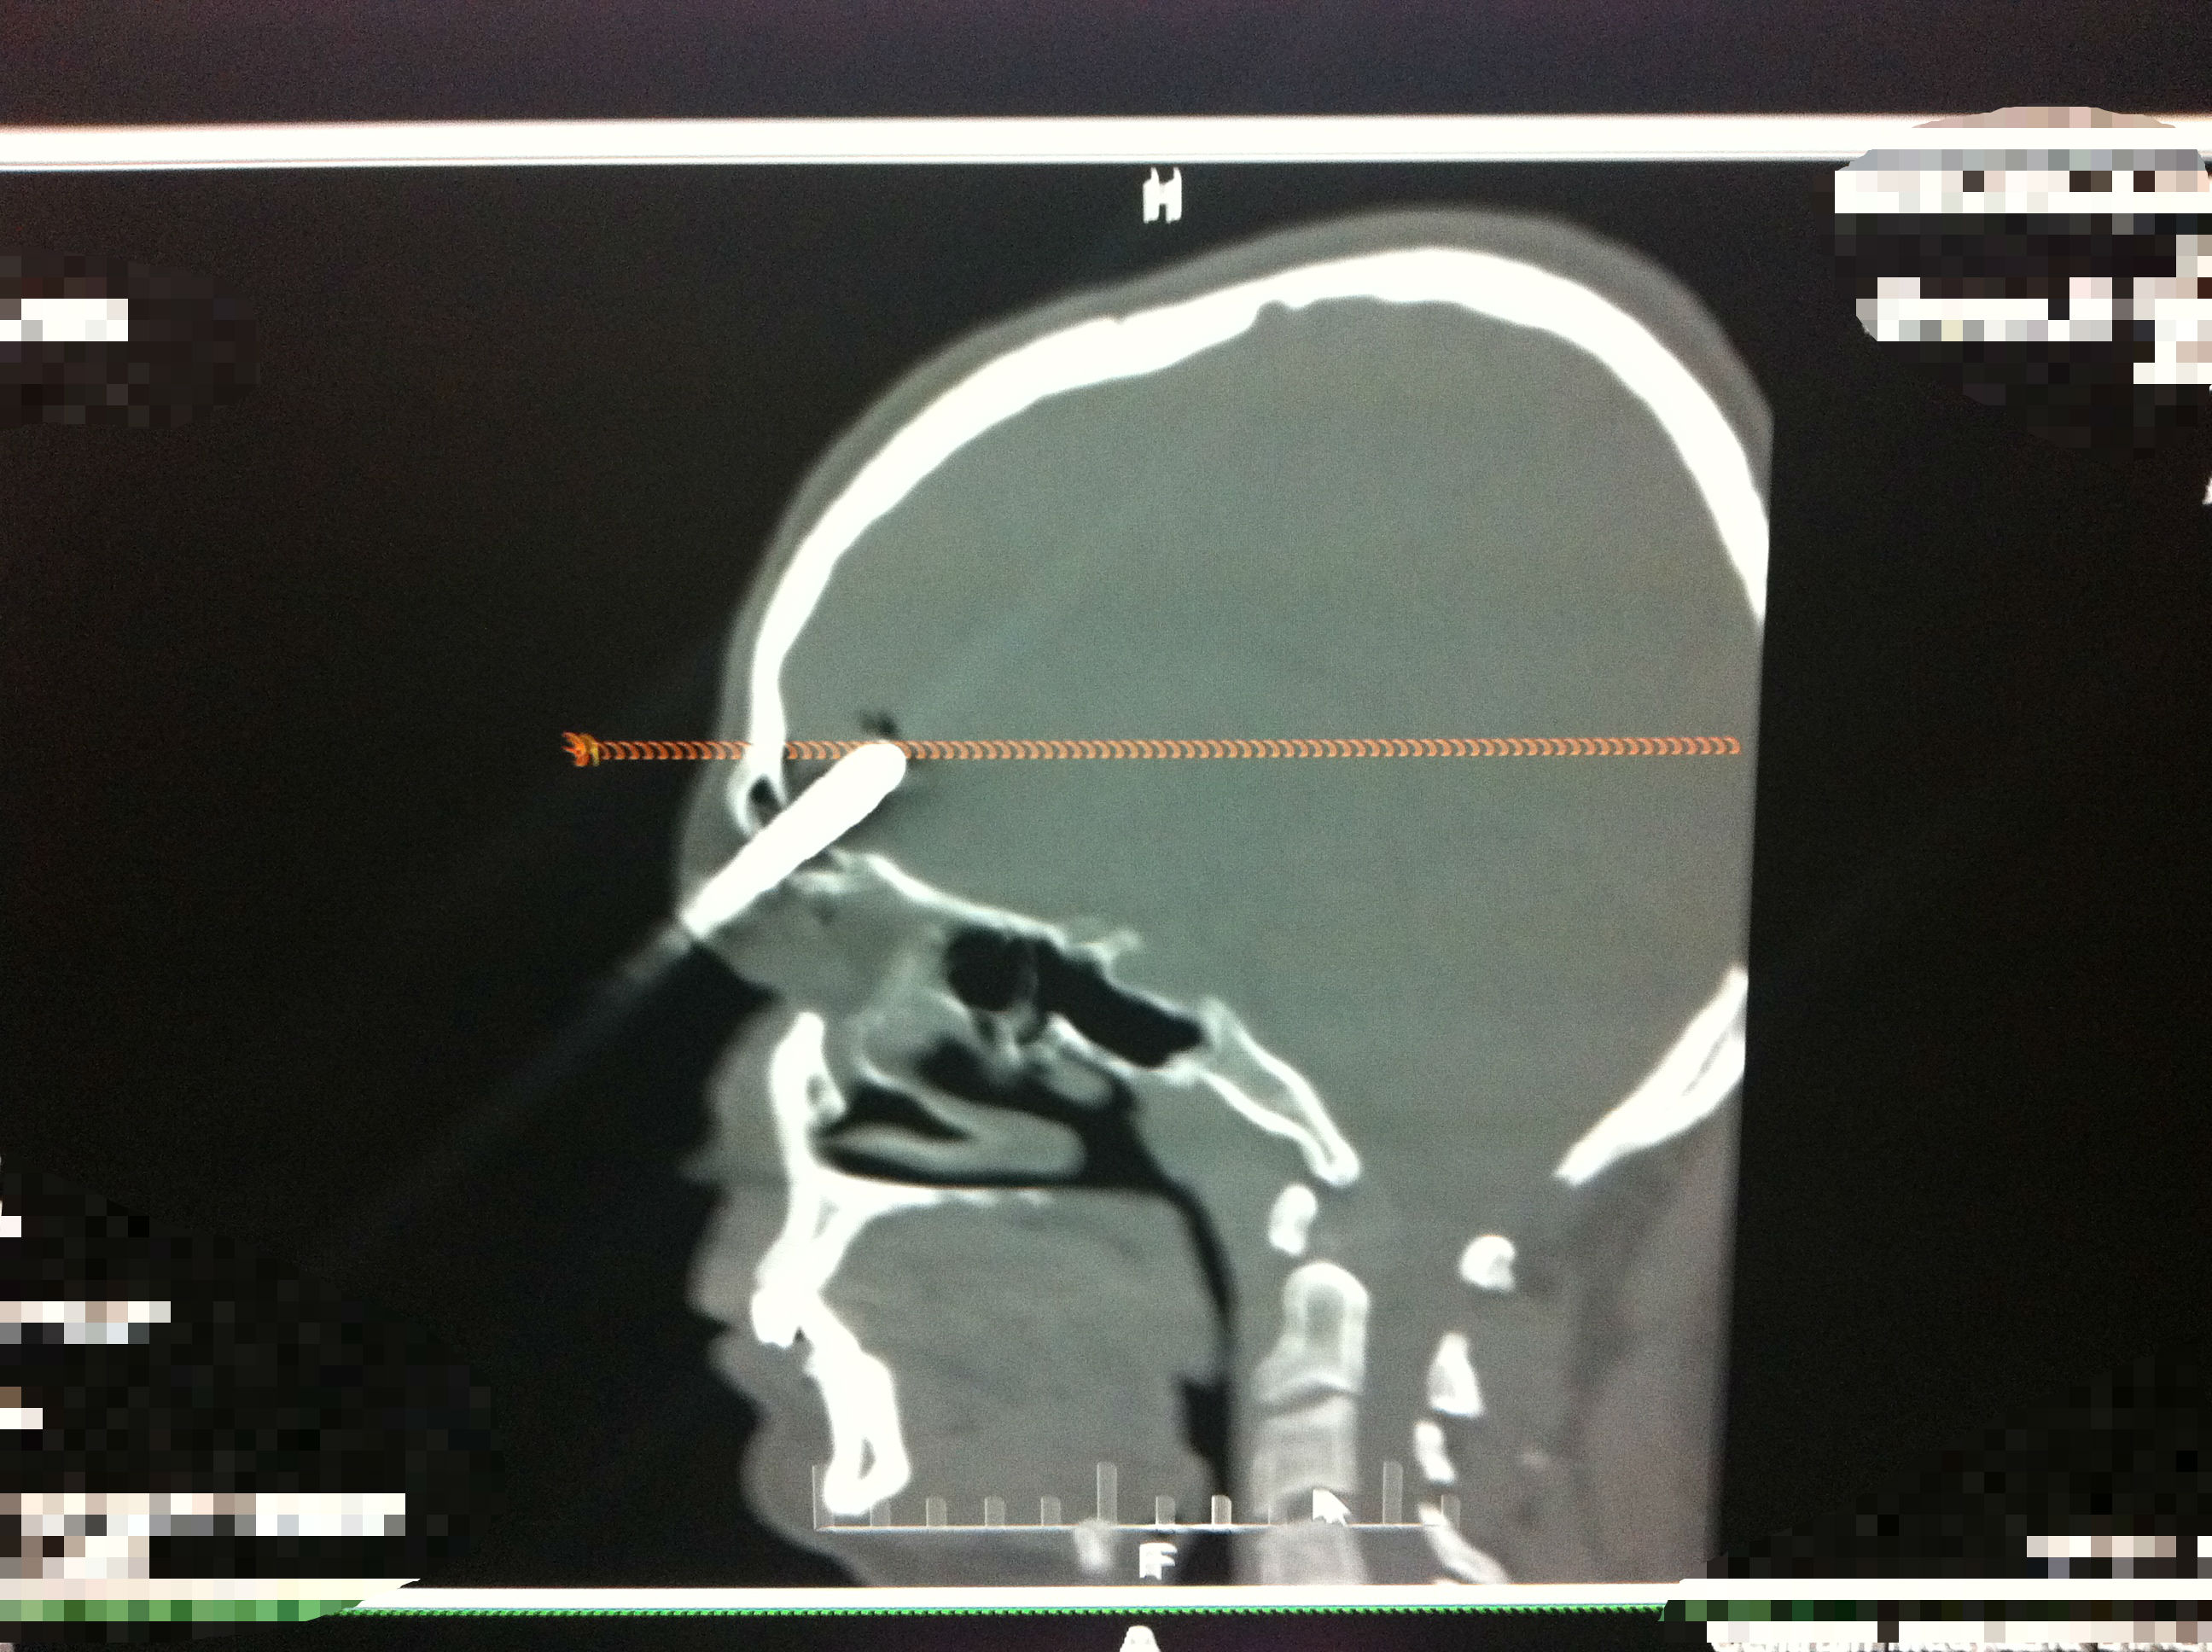

Mężczyzna z wbitym tuż nad prawym okiem śrubokrętem trafił do Kliniki Neurochirurgii Uniwersyteckiego Szpitala Klinicznego w Białymstoku. Lekarzom udało się usunąć ciało obce, a pacjent czuje się dobrze

Wypadek wydarzył się na początku marca. 25-latek z Łap majsterkował na podwórku przy domu. Prawdopodobnie, kiedy wchodził na drabinę, o coś się zaczepił i upadł. Zrobił to tak niefortunnie, że w czoło wbił mu się na głębokość ok. 5 centymetrów śrubokręt.

W Klinice Neurochirurgii 25-latek trafił od razu na stół operacyjny. Podczas trwającej trzy godziny operacji udało się usunąć śrubokręt. Okazało się też, że pacjent może mówić o ogromnym szczęściu, ponieważ w zasadzie nic mu się nie stało i rokowania na przyszłość też nie są niepokojące. Podczas wypadku nie został uszkodzony mózg. Dzięki pracy lekarzy pacjent wyjdzie ze szpitala tylko z niewielką blizną na czole.

- To był trudny przypadek. Najpierw trzeba było usunąć śrubokręt, a następnie zatamować wypływ płynu mózgowo-rdzeniowego i krwi - relacjonuje przebieg operacji dr Piotr Szydlik, neurochirurg z USK. - Śrubokręt tkwił w płacie czołowym, w sumie na głębokości około pięciu centymetrów. Zabieg był wykonany z tzw. dojścia małoinwazyjnego. Pacjent po zabiegu czuje się bardzo dobrze, wymaga tylko dalszego leczenia antybiotykowego.

Jak dodaje dr Jan Kochanowicz z Kliniki Neurochirurgii USK, płat czołowy mózgu, gdzie doszło do wbicia ostrza śrubokrętu, jest niemy klinicznie. - Oczywiście została uszkodzona część mózgu, czy też zatoka czołowa, ale ten fragment mózgu nie odpowiada za jakieś funkcje ruchowe czy za wzrok. Od oka było bardzo blisko, ok. centymetra